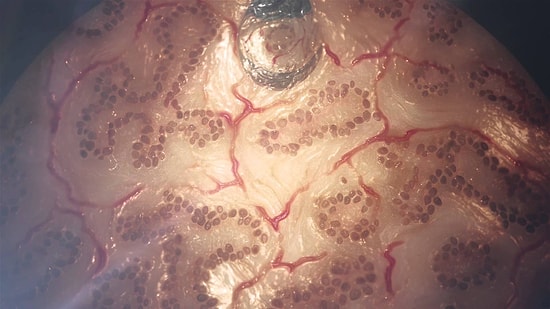

Türk Mucitten Cilt Kanserini 10 Saniyede Teşhis Eden Cihaz

ABD'deki MIT Üniversitesi'nden Dr. Dağdeviren, cilt kanserinin teşhisinde 10 saniyeden kısa sürede sonuç veren cihaz geliştirdi.Harvard Üniversitesi'ne 'Genç Akademi Üyesi' olarak kabul edilen ilk Türk olan Dr. Canan Dağdeviren, cilt kanserinin teşhisini kolaylaştıracak, dövme gibi vücuda yapıştırılabilen ve 10 saniyeden daha az sürede sonuç veren cihaz geliştirdi.Forbes dergisinin '30 yaşından küçük 30 bilim insanı' listesine giren Dr. Dağdeviren'in bu çalışması Nature Materials dergisinde yayımlandı. Cihazın, yapıştırıldığı deriye basınç uygulayarak derinin mekanik özelliklerini tespit ettiğini belirten Dr. Dağdeviren, 'Cihaz, bu özelliklerin kansere yakın olup olmadığını gösteriyor. Deri kanserinin mekanik özellikleri zaten belli. Bu özelliklere uyan sonuçlar çıktığı zaman biyopsi ve diğer prosedürler gerçekleştirilecek' dedi.Dr. Dağdeviren, cihazı kanser şüphesi olan hastalar üzerinde denediğini, doktorun da biyopsi yaptığını ifade ederek 'Ben kendi datalarımı yolladım. Tuhaf görünenleri kendisine söyledim. Biyopsi sonuçları iki hafta sonra çıktı ve benim söylediklerimle bire bir örtüştü. Bu yöntem hızlı, ağrısız ve de kolay bir yöntem. 10 saniyeden az bir sürede sonuç veriyor' diye konuştu. Cihazın kullanımıCihazın, dövme gibi vücuda yapıştırılabildiğini, çıkarılıp başka bölgeye de uygulanabileceğini belirten Dr. Dağdeviren, 'Vücut bunu hiç hissetmiyor, çok ince. Elektriksel bağlantılarla verileri bilgisayarda topluyoruz. Sonra bir program sayesinde vücudun mekanik özelliklerini gösteren renkli bir harita ortaya çıkıyor. Renklerle vücutta anormallik olan bölgeyi çok küçük bile olsa gösteriyor' ifadesini kullandı.